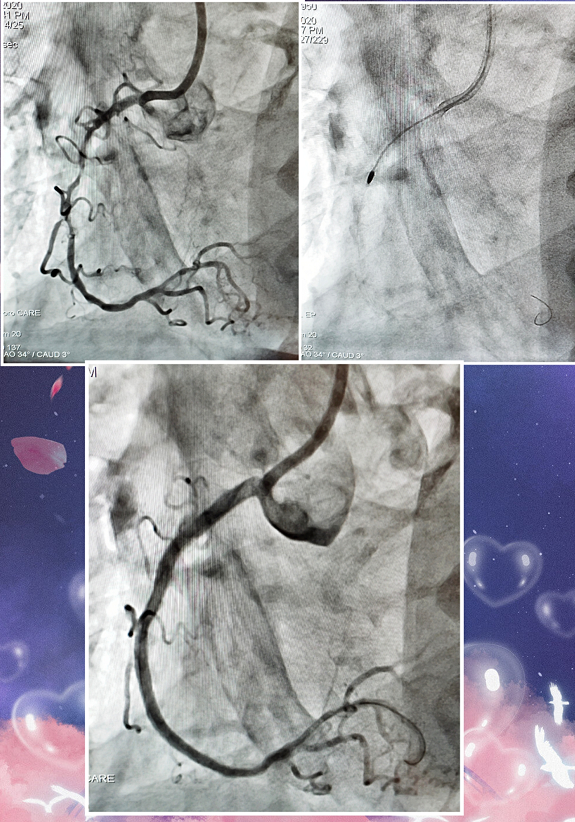

冠脉介入治疗中,严重的冠脉钙化病变对手术成功率和患者预后都有重要的影响,面对坚硬的钙化病变,旋磨预处理可以帮助开通管腔并修饰钙化病变,方便后续器械通过和支架扩张贴壁。FireRaptor(火猛禽)冠脉旋磨系统的创新开发,填补了国产器械在旋磨领域的空白,为中重度钙化病变的预处理提供了新选择。

上海微创表示,FireRaptor(火猛禽)冠脉旋磨系统将携手棘突球囊、冠脉冲击波导管系统,共同构建冠脉高阻力病变解决方案,为广大冠脉介入医生提供强有力的预处理工具。